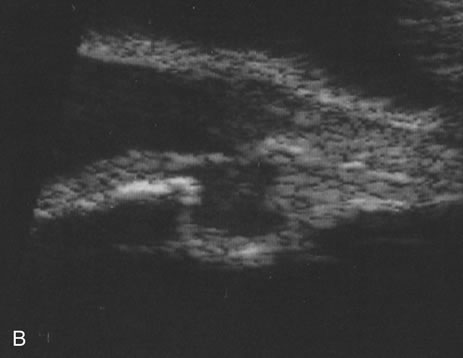

Necrotic melanomas account for approximately 5% of uveal melanomas; in the majority of cases, there is intraocular inflammation accompanying the cataract.7–9Figures 1 and 2 demonstrate a typical case. The patient had a long history of unilateral decreased vision. The eye had become painful 1 month before admission, and he was referred for evaluation of uveitis. Clinically, there was a dense, unilateral cataract with significant intraocular inflammation, which was manifested as a ciliary flush with 2+ cells and flare. Media opacity obscured all fundus detail. An immersion B-scan demonstrated a large intraocular tumor that was most consistent with a uveal melanoma. The eye was removed, and the diagnosis was confirmed histologically.10

Fig. 2. Immersion B-scan of the patient in Figure 1 demonstrates a uveal melanoma.